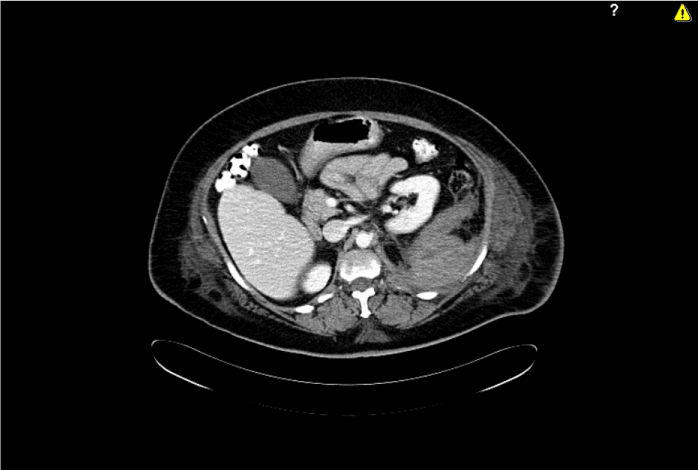

A new blood test showed a blood loss (haemoglobine 6.8 gr /dL) and a moderate leukocytosis (21.1x10 9 L-1). Under the suspicion of being in front of a diverticulitis we have ordered an urgent CT scan where a large retroperitoneal haematoma with anterior displacement of the left kidney (Figure 1) and diffusion of the haematoma into the left psoas and iliac muscles was seen suspecting an origin of the bleeding on the right lumbar artery (Figure 2).  A transfusion of three packed erythrocytes concentrate was performed urgently.

Figure 1. Urgent CT scan where a large retroperitoneal haematoma with anterior displacement of the left kidney was seen.